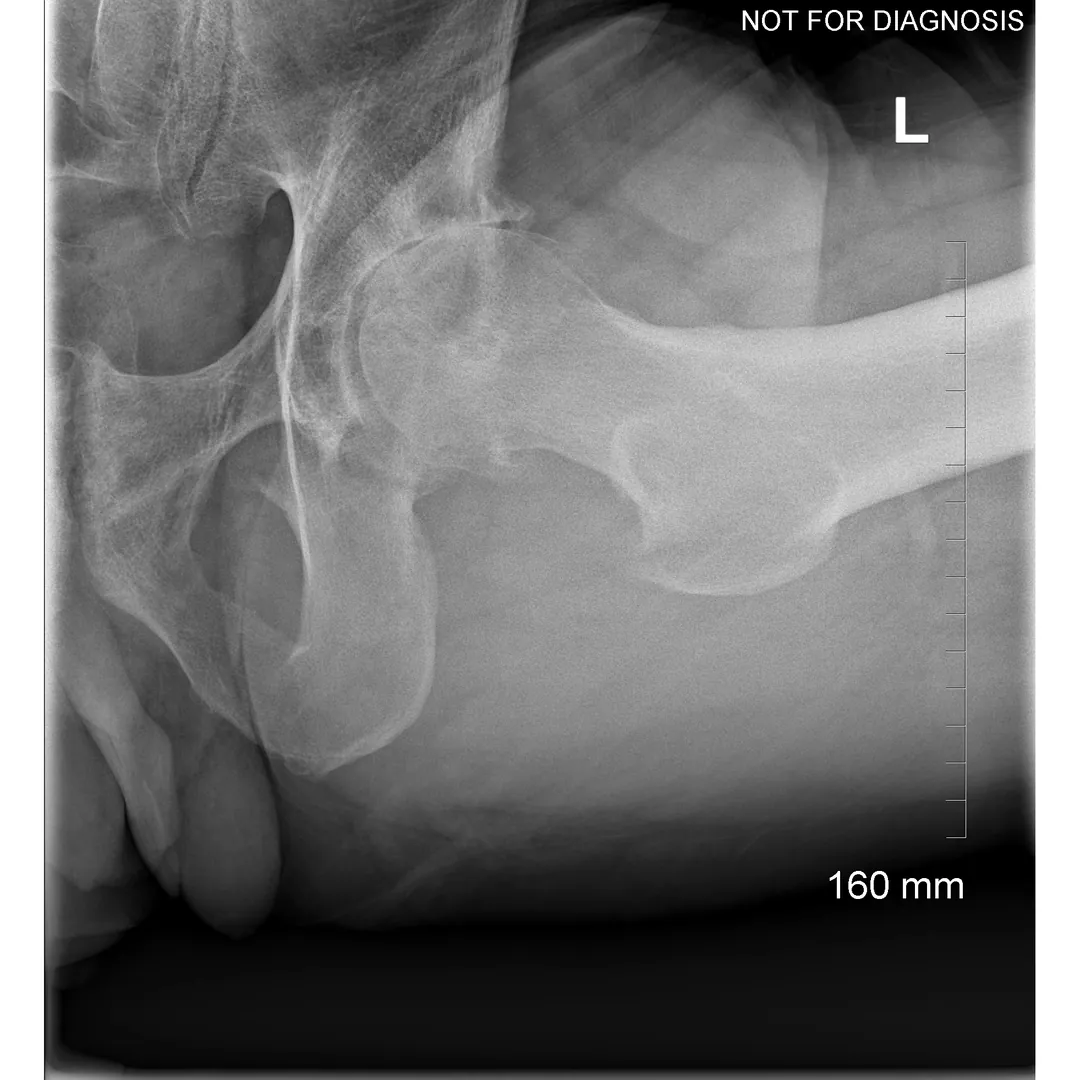

Hip resurfacing is a type of hip surgery used to treat hip arthritis, most commonly in younger and more active patients. Unlike a total hip replacement, hip resurfacing preserves more of your natural thigh bone. Instead of removing the entire femoral head (ball at the top of the thigh bone), the damaged surface is trimmed and covered with a smooth metal cap. The hip’s socket on the pelvis is also fitted with a metal cup.

- Have good bone quality and strong femoral neck bone

- Have a larger femoral head size

- Have minimal deformity of the hip joint

Dr Grammatopoulos will review your X-rays and other imaging carefully to determine whether hip resurfacing is an appropriate option for you.